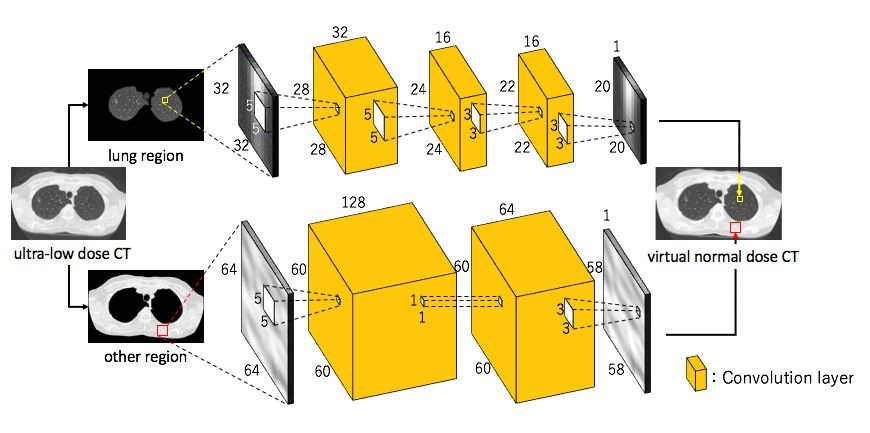

Because they produce 3D images of organs, bones, and blood vessels, computed tomography (CT or CAT) scans have significantly greater diagnostic value than simple X-rays. This added diagnostic value, however, comes at a cost: increased exposure to potentially harmful radiation. The 3D images produced by a CT scan are assembled from 2D X-ray images stacked together by computer software. As a result, a single CT scan of the chest has an average effective radiation dose of 7 milliseverts (mSv), 350 times higher than the chest X-ray dose of 0.02 mSv. [1] Radiation exposure is correlated with cancer risk; guidelines limit the radiation dose to 1.5 mSv in CT scans of children. Medical researchers want to limit radiation exposure while providing physicians with the image clarity they need. One promising approach is the use of ultra-low-dose CT, which has an effective average dose of about 0.13 mSv for a chest image. [1] The principal drawback of ultra-low-dose CT scans is their relatively low resolution and high level of noise, which can make it difficult for physicians to see organs, fat, and interstitial tissue (Figure 1). Figure 1. Comparing the image quality of ultra-low-dose CT (left) with a traditional CT (right). I have developed a MATLAB® software system based on convolutional neural network (CNN) regression that uses ultra-low-dose CT scans as input but generates images comparable in quality to a normal-dose CT scan. The system provides physicians with a comparable level of diagnostic information while reducing patient radiation exposure by as much as 95%. Super-Resolution vs. CNNsWhen I began researching ways to improve the quality of low-dose CT images, I applied a super-resolution technique in which I used MATLAB to divide CT images into small local regions and then paired low-dose and normal-dose regions to create an image dictionary. When a new low-dose image is to be analyzed, the system finds a small low-dose region in the dictionary and presents the corresponding normal-dose patch to the user. The technique’s effectiveness depends on having a huge dictionary from which to draw comparisons. However, increasing dictionary size increases the resource demands of the system and, more importantly, the search time needed to find small images. While a CNN takes time to train, when presented with a new image it produces results much faster than the super-resolution approach I developed. For example, a trained CNN can yield results in about 20 minutes for a single patient, whereas it took about 2 hours to obtain comparable results using super-resolution. Although I began exploring CNN regression to address the shortcomings of super-resolution, there are some cases in which the super-resolution technique performs very well. For example, when patterns in an image to be diagnosed closely resemble those in one of the dictionary images, the super-resolution approach produces highly accurate results. For this reason, I plan to create a hybrid system that combines CNN regression with super-resolution. Obtaining Images and Constructing the CNNsTo improve the clarity of ultra-low-dose chest CT scans, I applied an approach that uses two CNNs, one targeting the lung areas of the CT images and the other targeting the non-lung area (Figure 2). The image data set that I used to train the CNNs was provided by researchers at Mie University. It consists of 12 image pairs, each of which includes a normal-dose scan and an ultra-low-dose scan of the same tissue. (Because taking a second image means exposing a patient to additional radiation, we had to limit the study to a relatively small subject pool.) Each image in the study was 512 x 512 pixels, and each scan contained 250 images (slices).

Figure 2. CNNs trained on lung and non-lung areas of the ultra-low-dose CT.

I based the initial structure of the CNN on the results of my earlier work on super-resolution. In that study, I found that a local region of 7 x 7 worked best, and I began with that size local region for my deep learning model. I subsequently experimented with local region sizes between 5 x 5 and 128 x 128, checking the clarity of the results each produced, before settling on 32 x 32 for lung area and 64 x 64 for non-lung area. Working in MATLAB, I also evaluated about 128 different CNN variants, trying different input sizes and filters as well as various numbers of convolutional layers. Training and Validating the CNNsUsing cross-validation, I trained the model with images from 11 patients and tested it with images from the one remaining patient. I repeated these steps 12 times with different training sets and test images. To accelerate this process, I trained in parallel on multiple NVIDIA® GeForce series GPUs using Parallel Computing Toolbox™. To monitor training progress, I plotted accuracy and loss using the monitoring visualization option in Deep Learning Toolbox™ (Figure 3).